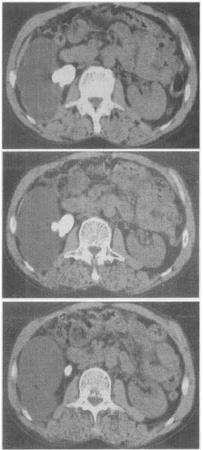

患者,女。48岁。反复血尿伴右侧腰痛7个月。CT扫描图像见图。最有可能的诊断是()。

A:肾囊肿

B:肾结核

C:多囊肾

D:肾脓肿

E:肾结石